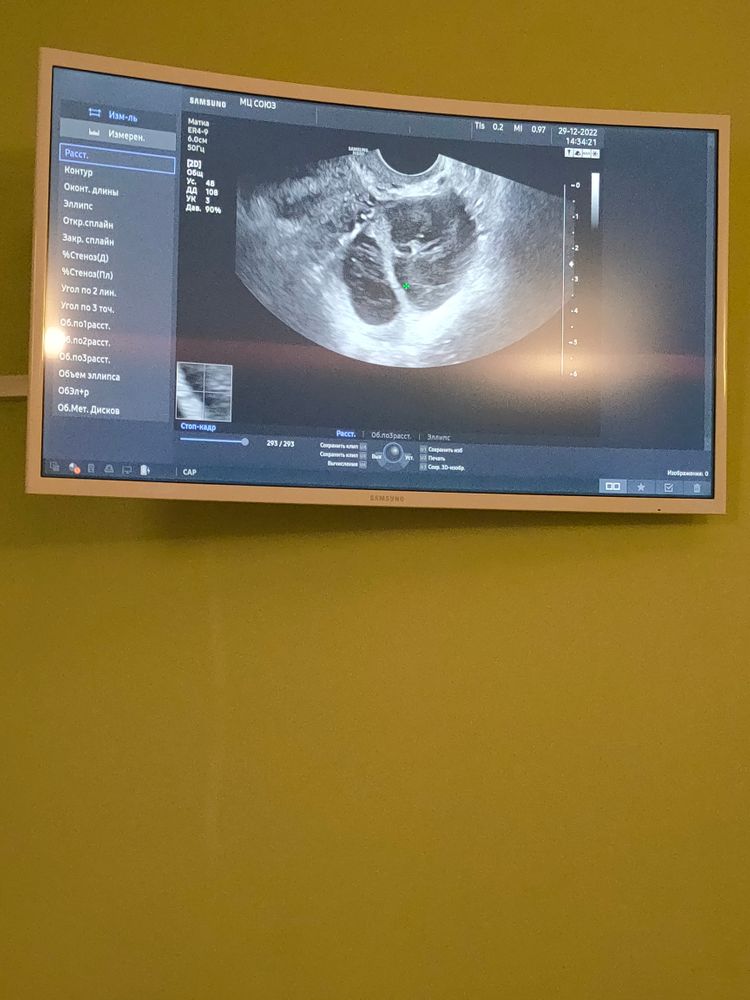

Геморрагическая киста яичника

Девчонки, у кого была геморрагическая киста яичника, что вы делали? Когда она уйдёт? Болит при резких движениях, когда резко встаю например, или чихаю. Задержка у меня уже неделя, месячные не начинаются видимо из-за тонкого эндометрия? В этот раз он просто тончайший - 6,5 мм.

Дополнение: сходила в клинику мать и дитя, оказалось это крупное желтое тело, овуляция была, но очень поздняя, на 26 дц, а на втором яичнике тоже должна была быть овуляция, но фолликул как бы не успел совулировать, поэтому ушел в фолликулярную кисту. В результате задержки-то и нет:)